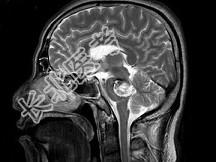

- 单项选择题男,42岁, 头晕视物旋转,面部麻木半月余, 根据所提供图像,最可能的诊断是 ( )

A、脑干动静脉血管畸形

B、脑干出血

C、脑干血管瘤

D、脑干胶质瘤并出血

E、脑干梗死